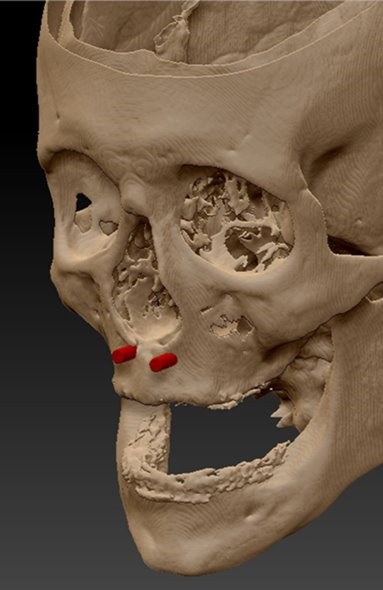

A strong Vertebrate Anatomy lecture class combined with a hands-on dissection lab will help prepare applicants for the science courses taken during the CA program. Learning anatomical terminology and scientific names is encouraged. Artists who have hands-on experience with dissection develop a tactile memory for the different organs, textures, locations and inter-relationships that will inform knowledge of those structures. While hands-on, student-performed, whole specimen, vertebrate dissection labs are encouraged, alternate labs are acceptable (see below).

Histology

Histology is the study of the different tissues of the human body at the microscopic level. Understanding the structures of the human body from the macroscopic (Anatomy) to the microscopic (Histology) levels will aid in anaplastology treatment planning.

Cancer, birth differences and traumatic incidences, the most common reasons patients seek the care of clinical anaplastologists, will impact different tissues in the body: bone, skin, muscle. Having a microscopic understanding of these tissues could influence patient care.